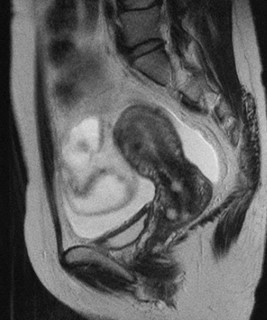

婦人科MRI検査の結果頚部に貯留嚢胞の所見がありました。頚部